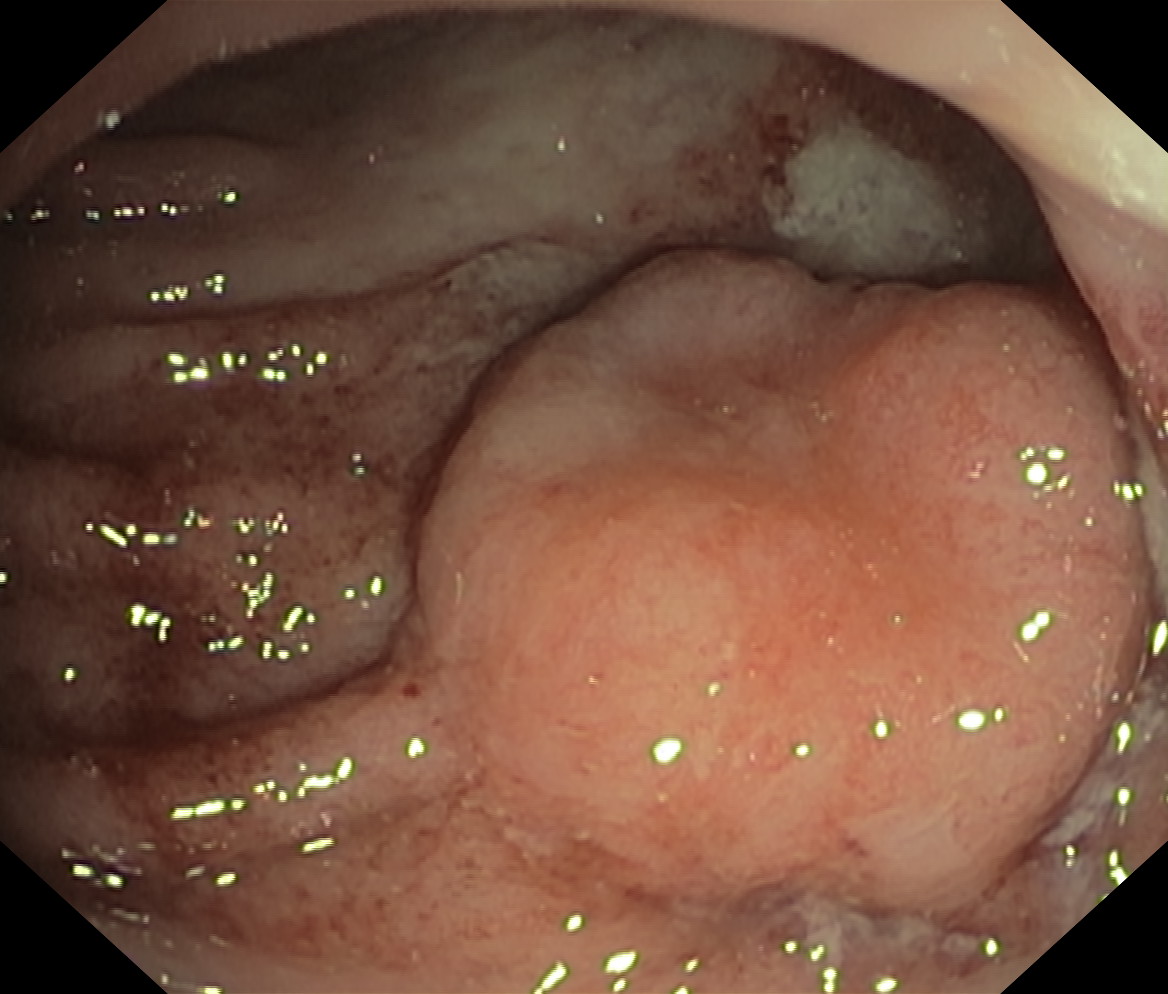

Nowotwory przewodu pokarmowego